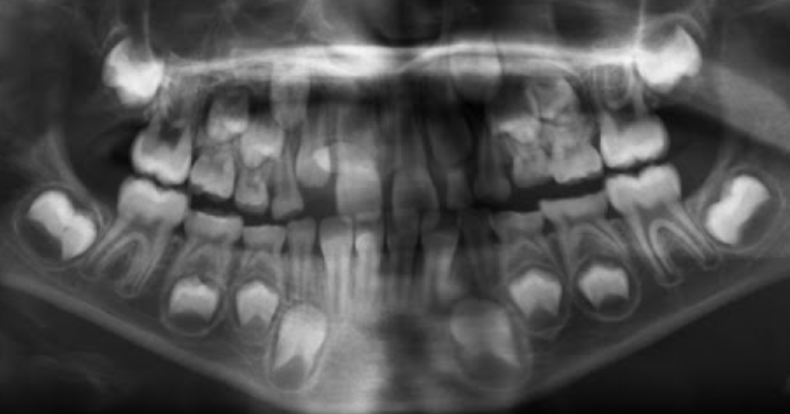

Permanent lower incisors present? Yes, so definitely 6-7

Permanent upper Incisors not erupted yet. Therefore not 7-8 y.o.

Conclusion = 6 y.o